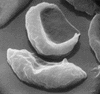

Blood smear in which the red cells show variation in size and shape typical of sickle cell anemia.

Photomicrograph of red blood cells, showing abnormal shape characteristic of sickle cell anemia.

Sickle cell anemia is caused by a variant type of hemoglobin, the protein in red blood cells that carries oxygen to the tissues of the body, called hemoglobin S (Hb S). Hb S is sensitive to deficiency of oxygen. When the carrier red blood cells release their oxygen to the tissues and the oxygen concentration within those cells is reduced, Hb S, in contrast to normal hemoglobin (Hb A), becomes stacked within the red cells in filaments that twist into helical rods. These rods then cluster into parallel bundles that distort and elongate the cells, causing them to become rigid and assume a sickle shape. This phenomenon is to some extent reversible after the cells become oxygenated once more, but repeated sickling ultimately results in irreversible distortion of the red cells. The sickle-shaped cells become clogged in small blood vessels, causing obstruction of the microcirculation, which in turn results in damage to and destruction of various tissues.